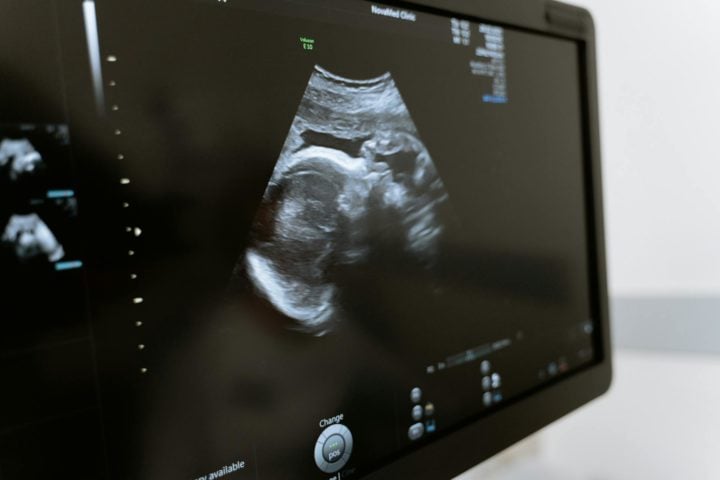

Embrião congelado em 1994 permite nascimento do ‘bebê mais velho do mundo’